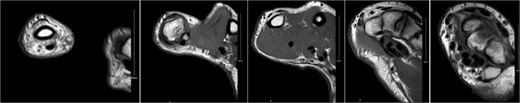

A 28-year-old female came to the emergency room (ER) following an MVA with airbag-deployment 5 days before presentation. Examination revealed tenderness at the base of the proximal fifth finger. The ROM of the affected digit was limited, but the neurovasculature as well as flexor digitorum profundus and flexor digitorum superficialis function were intact. X-ray of the hand showed a minimally displaced fracture at the base of the proximal fifth phalanx extending into the articular surface (Fig. 5). The decision was made to manage the patient conservatively by applying an ulnar gutter splint, which was then changed to a volar splint when the patient was followed-up in the clinic a week later. When the patient was last seen, the patient had limited ROM, and the tenderness had resolved. Imaging showed evidence of ongoing healing (Fig. 6).

A minimally displaced fracture at the base of proximal fifth phalanx extending into the articular surface.